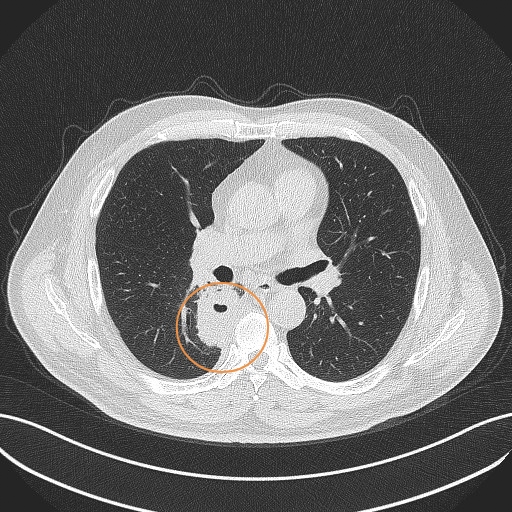

一个肺脓肿患者,差点被误诊为肺癌 这个病人50岁,咳嗽,咳痰四五天了